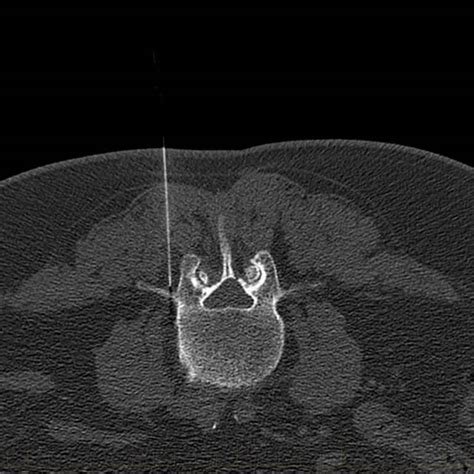

A Medial or Lateral Branch Block is a procedure performed under CT guidance to precisely place a needle near the targeted nerve. Our Radiologist will inject a small amount of local anesthetic to temporarily ‘block’ the nerve from sending pain signals.

A medical scan image of a pelvis, showing bones and internal structures.

CT Guided Branch Block